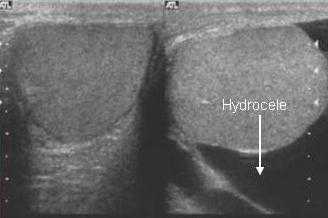

Гидроцеле - скопление жидкости между листками влагалищной оболочки. Серозная жидкость может накапливаться внутри влагалищной оболочки по разным причинам, которые включают инфекции, травмы, нарушение закрытия влагалищного отростка и др.

УЗИ яичек при водянке яичка дает возможность диагностировать гидроцеле в виде анэхогенного образования внутри мошонки.

На ультразвуковом изображении слева визуализируется нормальное яичко, окруженное влагалищной оболочкой. Справа яичко окружено гидроцеле - между париетальным и висцеральным листками находится большое количество жидкости.

Гидроцеле может быть настолько большого размера, что при пальпации врач не может определить нахождение яичек. В этом случае УЗИ помогает определить локализацию яичка.

Гидроцеле заполнено серозной жидкостью, именно поэтому при УЗИ оно имеет анэхогенную структуру. Если в полость гидроцеле попадает кровь, такое патологическое состояние носит название гематоцеле. Гематоцеле может возникать в результате травмы мошонки, перекрута, опухолевой инвазии. Пиоцеле - это скопление гноя в полости гидроцеле из-за присоединения инфекции. При УЗИ пиоцеле и гематоцеле - это эхогенные образования, в полости которых со временем могут появляться перегородки, уровни жидкости.

На рисунке слева показано гидроцеле, заполненное серозной жидкостью. А справа визуализируется гематоцеле с большим количеством перегородок.